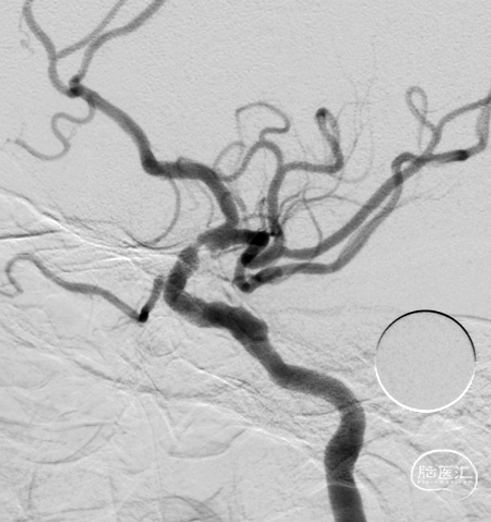

术前影像

报告描述:

1、双侧颈总动脉、颈内动脉、颈外动脉及锁骨下动脉血流速度及频谱形态大致正常。

2、右侧大脑中动脉血流速度增快、流速达219cm/s、有涡流杂音,左侧大脑中动脉、双侧大脑前动脉、大脑后动脉血流速度及频谱形态大致正常。

3、双侧颈内动脉虹吸部血流速度增快、流速达(L175cm/s,R124cm/s)、有涡流杂音,双侧眼动脉血流速度及频谱形态大致正常。

4、双侧椎动脉及基底动脉血流速度及频谱形态大致正常。

5、双侧桡动脉血流速度及频谱形态大致正常。

6、分别压同侧颈外动脉分支,双侧滑车上动脉血流速度均增快。

提示:

1、右侧大脑中动脉狭窄。

2、双侧颈内动脉虹吸部中度狭窄。

左右滑动切换图片

右侧大脑中动脉M1分叉处局部重度狭窄,约80%。